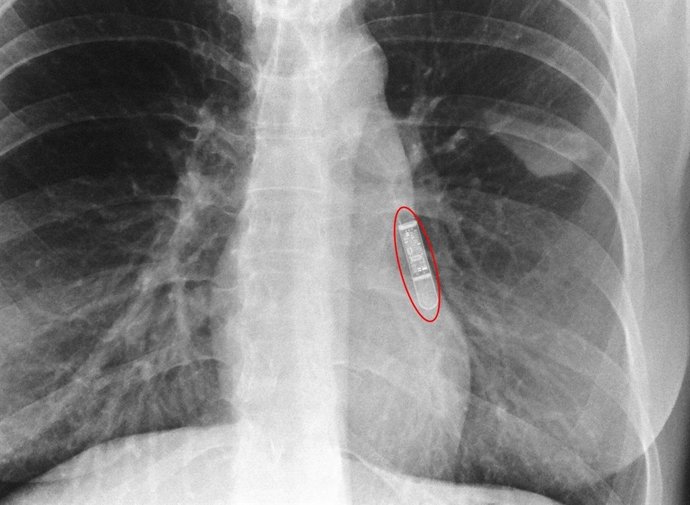

Imagen radiológica tras la implantación.

La novedad del dispositivo implantado por primera vez en el Complejo Hospitalario de Navarra es su reducido tamaño (más pequeño que el capuchón de un bolígrafo), lo que permite que su implantación pueda hacerse sin utilizar bisturí como hasta ahora, y, por tanto, sin puntos de sutura que deban ser retirados con posterioridad. Así, el Holter se implanta a través de una mínima incisión de tan sólo unos pocos milímetros mediante la inyección del aparato debajo de la piel.